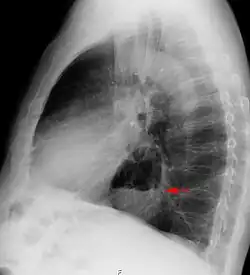

Normallage

Anatomisch normal verläuft die Speiseröhre durch den Brustraum vom Rachen bis zum Zwerchfell (siehe Abbildung, Buchstabe A). Dort tritt der unterste Teil der Speiseröhre durch das Zwerchfell hindurch in den Bauchraum. Direkt unterhalb des Zwerchfells mündet die Speiseröhre in den Magen. An diesem Übergang liegt der sogenannte untere Ösophagussphinkter (UÖS), der ein Rücklaufen des Mageninhalts in die Speiseröhre verhindert. In der anatomischen Normalsituation wird dieser Verschlussmechanismus durch die Muskelspannung des Zwerchfelles unterstützt.

Grün ist die Speiseröhre, rot das Zwerchfell, schwarz der Magen, blau der His-Winkel.

A ist anatomisch normal, B ist eine kardiofundale Fehlanlage, C ist eine axiale Hernie, D eine paraösophageale Hiatushernie

Es gibt verschiedene Varianten der Hiatushernie: Die kardiofundale Fehlanlage (siehe Abbildung, Buchstabe B) ist die leichteste Form und stellt einen häufigen Zufallsbefund bei Gastroskopien dar. Bei dieser Fehlbildung ist der Cardia-Bandapparat, der den Magen mit dem Zwerchfell verbindet, gelockert. Medizinisch-anatomisch ist die kardiofundale Fehlanlage durch einen stumpfen ösophagogastralen Winkel (= His’scher Winkel) gekennzeichnet (anders als bei der anatomischen Norm, bei der dieser Winkel spitz ist, siehe Abbildung). Klinisch bereitet dieser Zustand nur in den seltensten Fällen Beschwerden.

Die axiale Hernie (siehe Abbildung, Buchstabe C) – auch Gleitbruch genannt – ist mit 90 % die häufigste Form der Hiatushernie. Dabei tritt der oberste Anteil des Magens durch das Zwerchfell nach oben in den Brustraum (wie z. B. bei einer Hernie des Zwerchfells). In dieser krankhaften Situation kann der untere Verschluss der Speiseröhre nicht mehr durch das Zwerchfell unterstützt werden. Dadurch kann es zum Reflux, also dem Zurückfließen von Mageninhalt in die Speiseröhre, kommen. Dies kann unter anderem zu Refluxösophagitis (Sodbrennen) führen. Allerdings sind auch bei dieser Form 90 % der Betroffenen beschwerdefrei und benötigen keine weitere Therapie.

Die paraösophageale Hiatushernie (siehe Abbildung, Buchstabe D) zeichnet sich aus durch die anatomisch korrekte Lage des unteren Ösophagussphinkters (Schließmuskel der Speiseröhre) und dessen uneingeschränkte Funktion. Ein Teil des Magens schiebt sich jedoch von unten in den Brustraum. In der äußersten Form dieser Hiatushernie kann auch der ganze Magen oberhalb des Zwerchfells liegen (Upside-Down-Stomach oder Thoraxmagen). Im klinischen Verlauf beginnt die paraösophageale Hiatushernie mit einem asymptomatischen Stadium. Es folgt das unkomplizierte Stadium, mit Aufstoßen und Druckgefühl in der Herzgegend. Diese Symptome treten vor allem nach der Nahrungsaufnahme auf. Danach kommt es zum Komplikationsstadium mit Passagestörungen, Inkarzerationen, Geschwüren und Blutarmut infolge chronischer Blutungen.